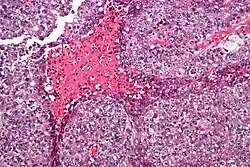

| Micrograph of an embryonal carcinoma showing its typical features – prominent nucleoli, marked nuclear atypia, necrosis, and nuclear overlap. H&E stain. | |

The gross examination usually shows a two to three centimetre pale grey, poorly defined tumour with associated haemorrhage and necrosis.[3]

The microscopic features include: indistinct cell borders, mitoses, a variable architecture (tubulopapillary, glandular, solid, embryoid bodies – ball of cells surrounded by empty space on three sides), nuclear overlap, and necrosis.